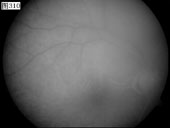

[组图]优秀眼底图片奖网上评选活动启动         ★★★

优秀眼底图片奖网上评选活动启动

优秀眼底图片奖应征作品展示